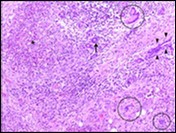

Figure 3.Granulomatous mastitis with scattered langhans and foreign body giant cells, epitheloid cell granuloma and lymphoid ingress11.

Granulomatous mastitis with               scattered langhans and foreign body giant cells, epitheloid cell granuloma and lymphoid ingress11.

Core needle biopsy of idiopathic granulomatous mastitis enunciates multiple aggregates of non- caseating epitheloid cell granulomas within and encompassing breast lobules, constituted of epitheloid histiocytes, lymphocytes, neutrophils and multinucleated giant cells. Granulomatous inflammation is predominantly lobulo-centric. The inflammation is preponderantly composed of lymphocytes, plasma cells, epitheloid histiocytes, multinucleated giant cells and neutrophils. Neutrophils can configure micro-abscesses and encompass vacant micro-cystic cavities, morphological features which are in common with cystic neutrophilic granulomatous mastitis. Non specific lobulitis along with a lymphoid and plasma cell infiltrate accompanies the granulomatous inflammation. Necrosis is usually absent. Neutrophilic micro-abscesses can be accompanied by fistula formation 4, 5.

Multinucleated giant cells are detected in an estimated three fourths (78.5%) instances. Plasma cells are discernible in around half (53.9%) of the subjects and usually appear at the margins of cystic vacuoles with centric accumulation of neutrophils within the granulomas.